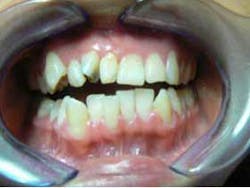

She came to me for an orthodontic consultation. She was 24 years old and hoping to marry her then-boyfriend at some point, but she didn't like her smile; she felt it was unattractive. So we gathered her orthodontic records and pointed out to her that it appeared she had either a supernumerary tooth or over-retained primary tooth between her upper centrals. Along with this, she also had some minor crowding on her lower teeth. She had a Class I molar relationship that I hoped to maintain.